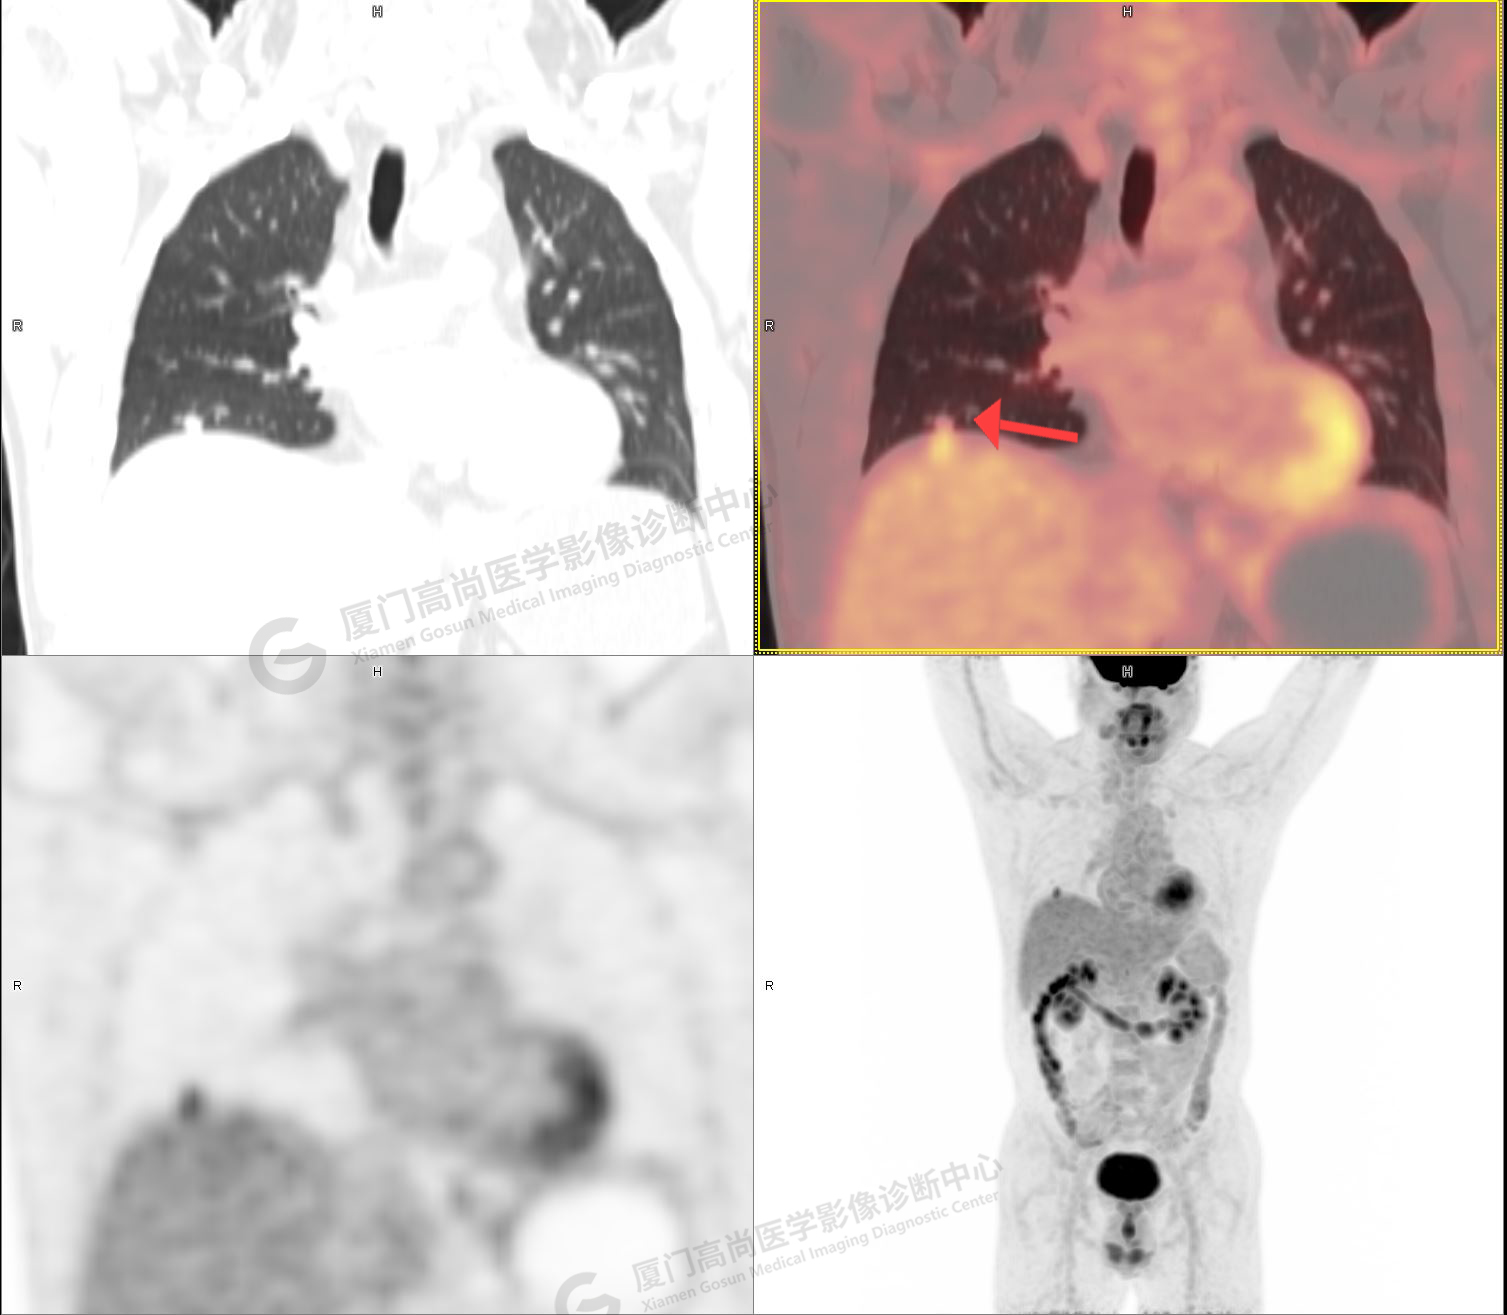

PET/CT影像圖

圖1

圖2

PET/CT示:1、左肺上葉混雜磨玻璃結(jié)節(jié),代謝不高,考慮為浸潤性腺癌,建議病理學(xué)檢查。2、右肺中葉混雜磨玻璃結(jié)節(jié),代謝不高,考慮為腫瘤性病變(微浸潤性腺癌?),建議密切CT復(fù)查。3、右肺上下葉純磨玻璃結(jié)節(jié),代謝不高,雙肺下葉少許結(jié)片影,代謝不高,考慮為炎癥。